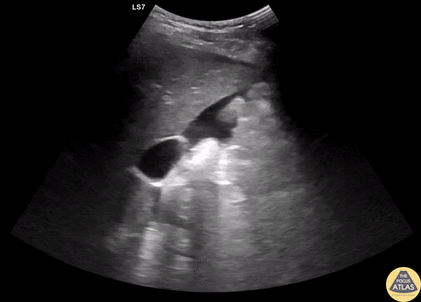

Trauma - +FAST in Morrison's Pouch from Splenic Injury

20s M presented with abdominal and back pain several hours after a fall off a ladder, and on FAST exam, had free fluid seen here in Morrison’s pouch, as well as a large amount of free fluid seen in the pelvis/lower abdomen. He was slightly tachycardic but normotensive, so underwent CT of the abdomen/pelvis, which demonstrated a significant spleen injury which was managed by IR embolization. Dr. Greg Wiener, PGY3 Denver Health Residency in Emergency Medicine